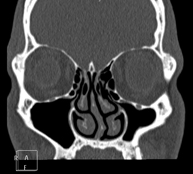

Prueba radiológica que consiste en obtener imágenes de los huesos maxilares de alta definición anatómica (piezas dentarias, trayecto del nervio dentario), mediante el empleo de un equipo de TC (Tomografía Computarizada). Indicaciones: estudio previo a la extracción dental, estudio previo a implantes, tumores, absceso. - TC Senos paranasales

Prueba radiológica que consiste en obtener imágenes de los senos paranasales de alta definición anatómica, mediante el empleo de un equipo de TC (Tomografía Computarizada). Indicaciones: cefalea, tos crónica, mucosidad, infecciones faciales. - TC Peñascos